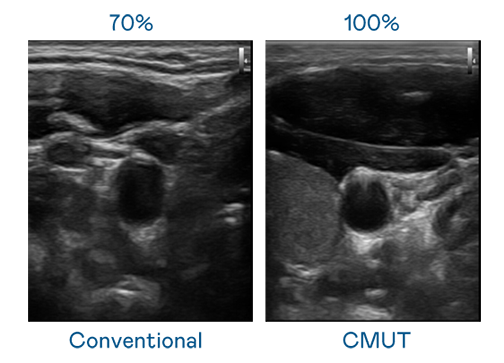

CMUT 技術是一種用電容式微機電元件來產生超音波訊號的技術。與傳統 PZT 壓電式技術相比,CMUT 頻寬增加 30%,更寬頻的超音波訊號讓影像解析度大幅提升,是實現高影像品質醫療超音波掃描、促進精準醫療發展的關鍵技術。

超音波影像的解析度高低,首先取決於探頭能發出的訊號頻寬。G22恒峰 CMUT 可提供高清晰的超音波訊號,提供高頻寬、高靈敏度、影像紋理細節更高的超音波影像,協助醫護人員縮短影像判讀時間及利用精準的醫療影像進行診斷。